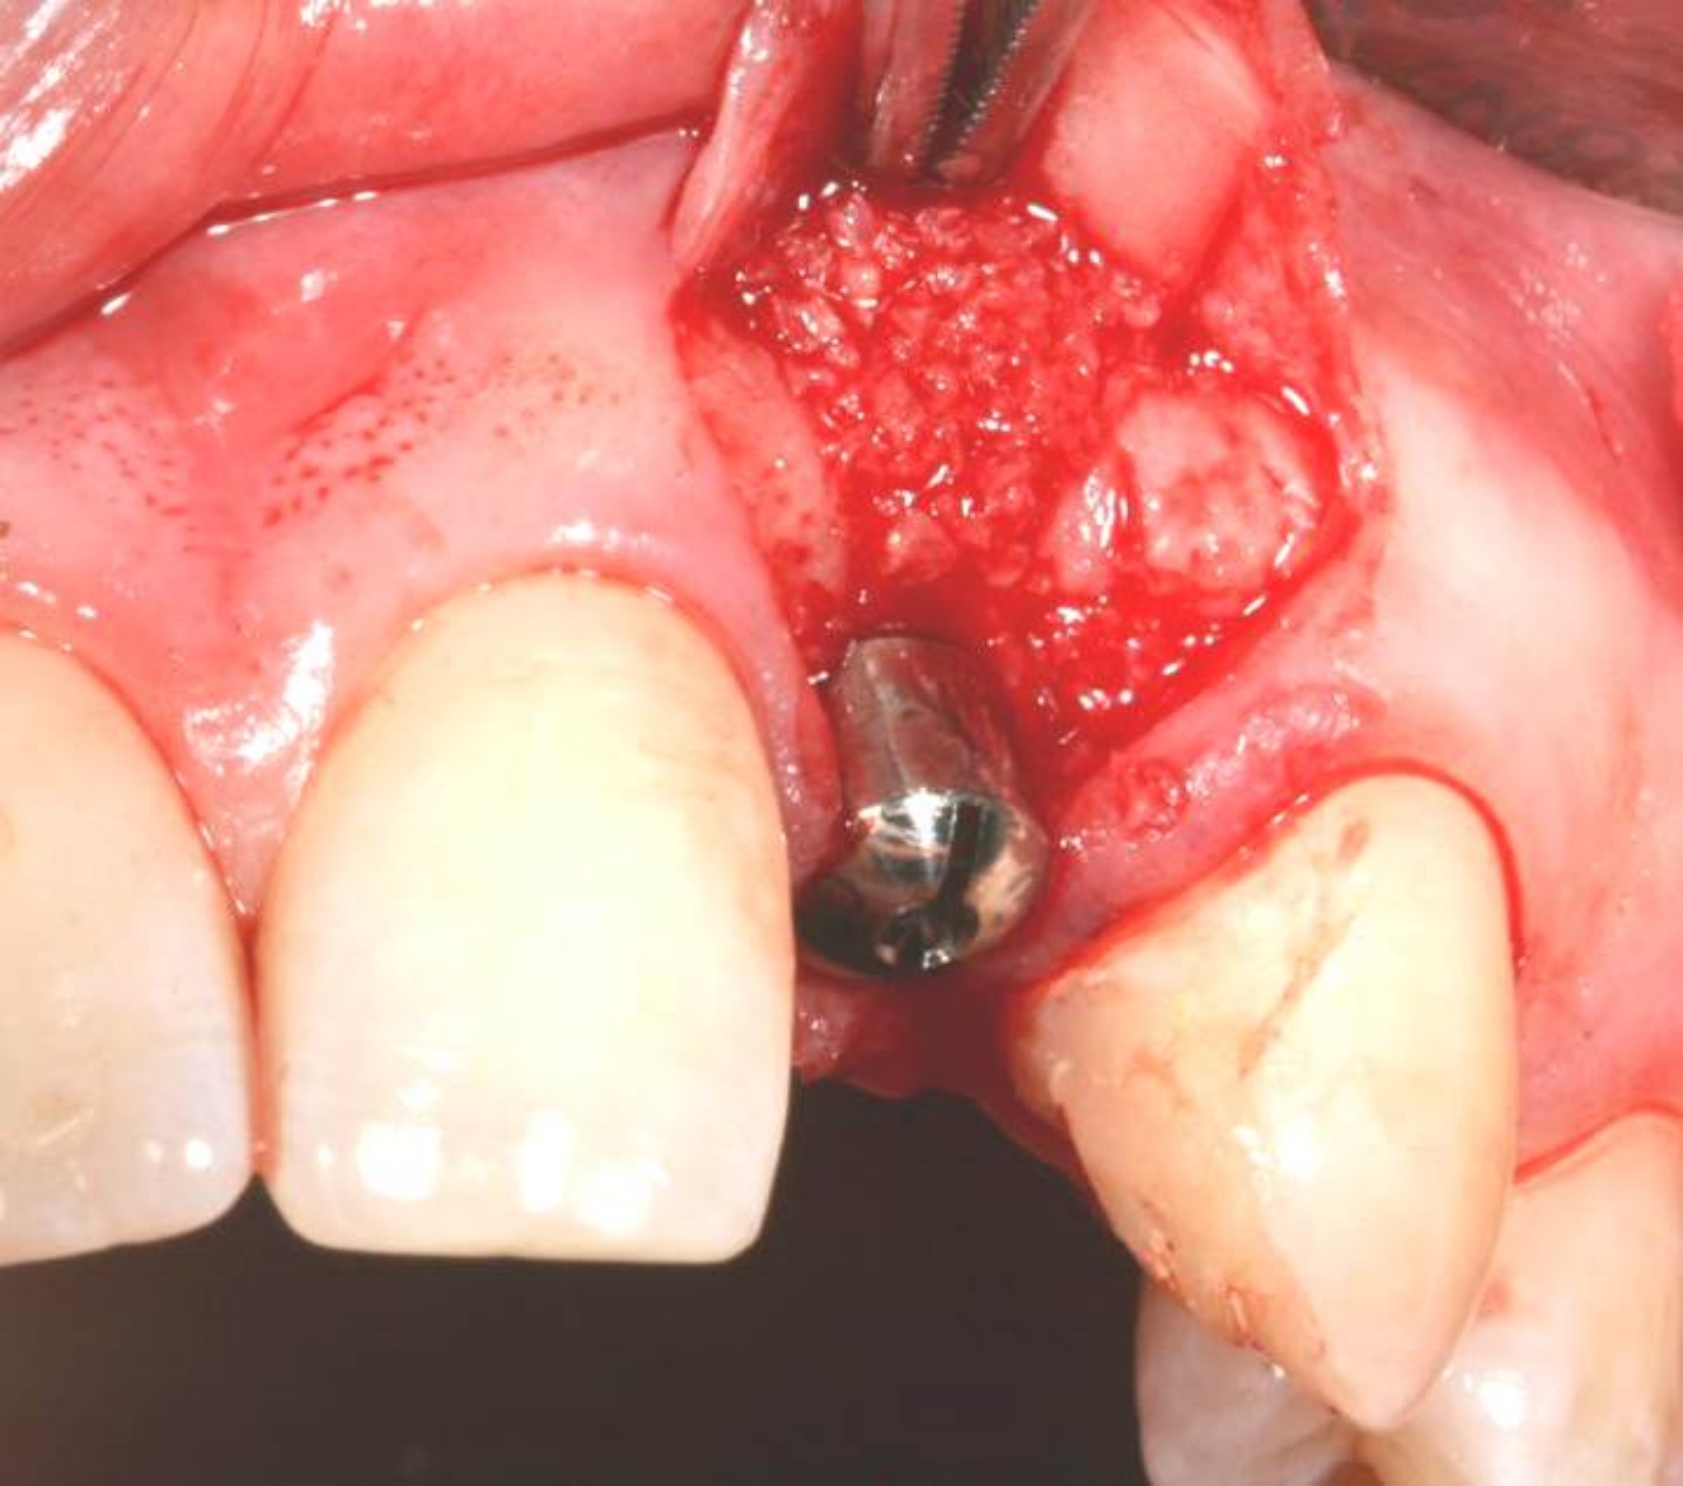

Fig 4. Implant inserted into the ridge, buccal view. There was a large labial concavity. The implant is seen on the buccal and terminates within the alveolar bone.

Figure 4

Fig 5. Bone graft placed over the implant on the buccal aspect.

Figure 5

Fig 6. Collagen barrier positioned over bone graft.

Figure 6